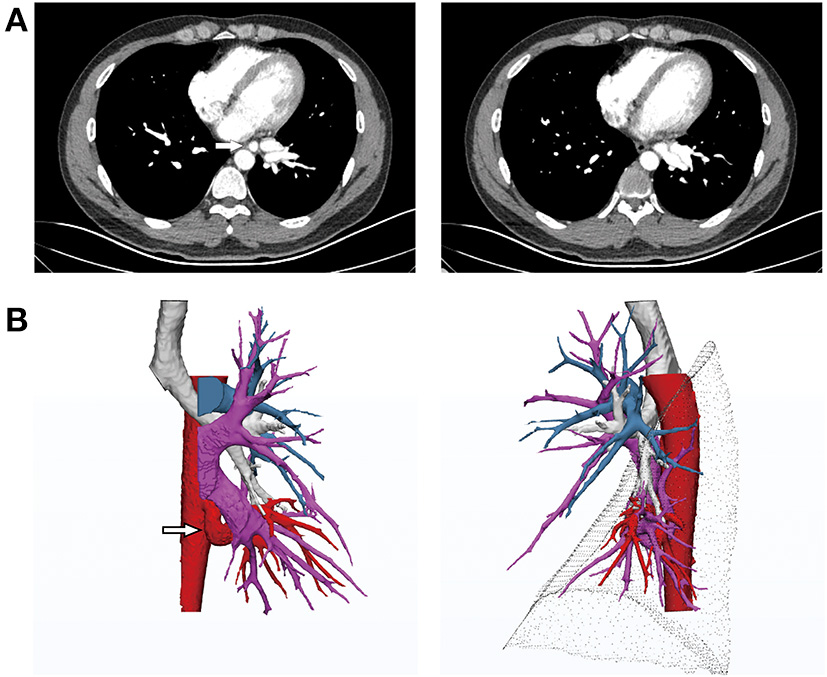

A 29-year-old man with intermittent hemoptysis (10 ml/episode) after physical activity sought treatment 1 year ago at our hospital. He became tired easily after regular physical activity. Computed tomography angiography (CTA) and three-dimensional computed tomography (3DCT) reconstruction showed a robust artery arising from the descending aorta, which was adjacent to the inferior pulmonary vein and approximately 2 cm in diameter. Branches of the artery intertwined with the inferior pulmonary vein in the basal segments. The superior segmental artery was present, whereas the basilar arterial trunk was absent. The structure of the bronchus in the left lower lobe was normal, and no lung tissue sequestration was noted (Figure 1). After consulting with the radiologist, it was determined that the superior segment was supplied by the pulmonary artery and that the basal segments were supplied by an abnormal systemic artery. The overall development of the patient was normal, and no obvious murmur was detected via auscultation of the heart and lungs. Ultrasonography revealed no abnormalities in the structure or function of the heart, and pulmonary function was normal.

Figure 1

(A) Computed tomography angiography (CTA) before treatment revealing the anomalous systemic artery. (B) 3D reconstruction indicating normal development of the left bronchus. The anomalous systemic artery originated from the descending thoracic aorta and branched to the basal segments of the left lower lobe, parallel to the left inferior pulmonary vein. The pulmonary artery of the left lower lobe was absent from the basal segments and only present in the superior segment.